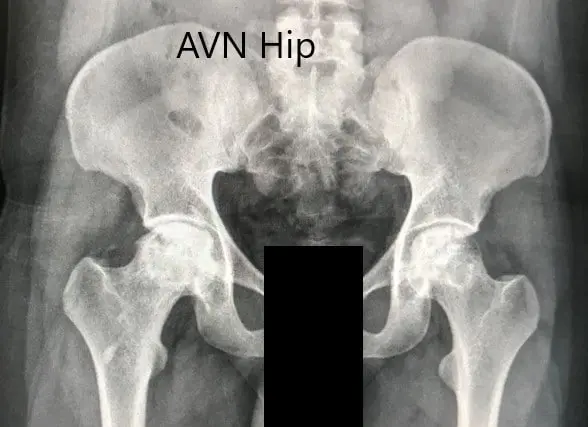

An X-ray was obtained which suggesting bilateral sclerosis of the head of femur and acetabulum changes. There were degenerative changes. An MRI of both hips was obtained.

Preoperative X-ray of the pelvis with both hips in anteroposterior view showing AVN of both hips.